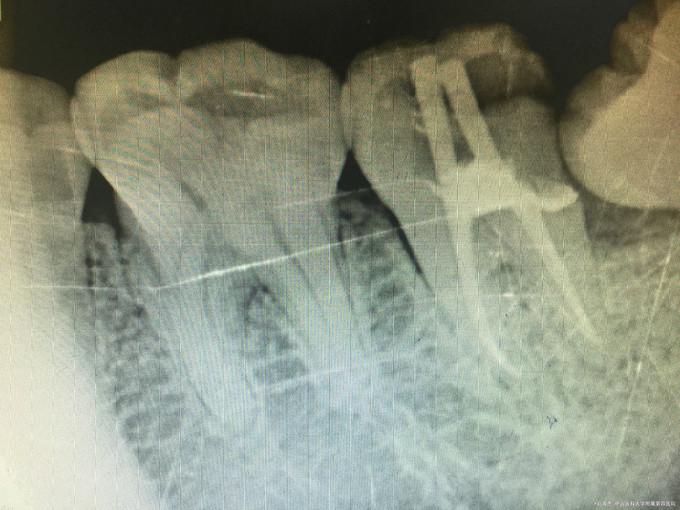

临床检查:37远中邻面龋坏,探疼(+),冷(++),叩(-),松动度(-),牙周正常. 38阻生齿未完全萌出。 辅助检查:X线示37龋坏累积髓腔,38近中阻生。

诊断:37牙髓炎,38阻生齿。 治疗:经患者知情同意后,37局麻去腐降牙合,开髓拔髓寻找根管口,建立直线通路,扩通根管,确定工作长度。vdw/EDTA凝胶镍钛器械,低浓度次氯酸钠冲洗根管,预备至25/06,氢氧化钙诊间封药,一周后复诊,试主尖X线示恰充,试干根管,导AH-PLUS糊剂,VDW热压胶垂直加压根充,术后见根管恰充,暂封调合抛光。择期拔除38.